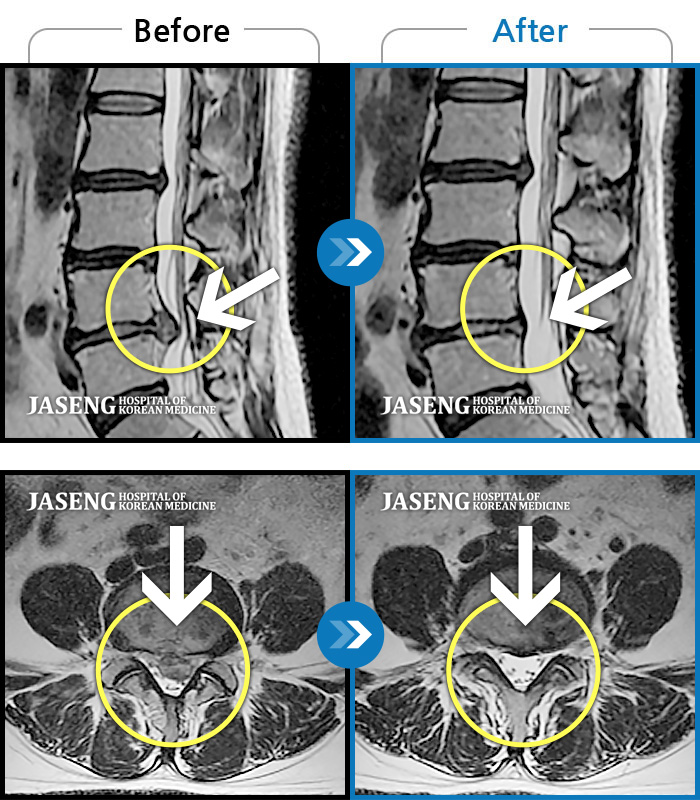

허리디스크

안산 · 김민수 원장

허리가 아프고 두 다리가 저려서 조금만 걸어도 주저 앉아야 했습니다.

촬영시기

2018.12.20 ~ 2023.02.21

2023.02.24